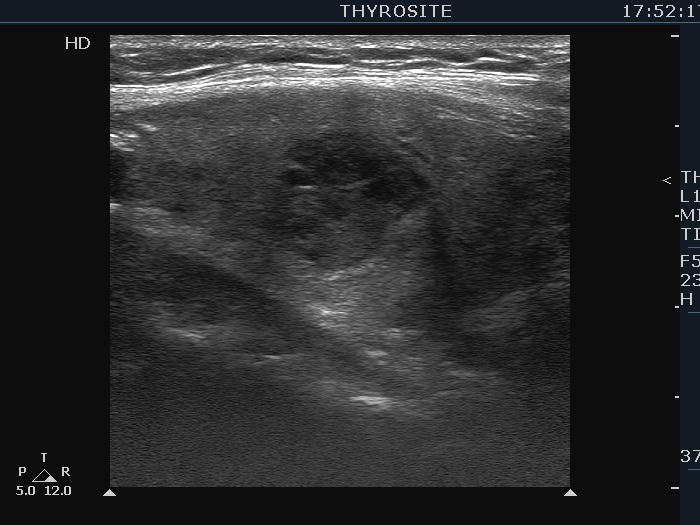

One year after the first examination (second row of images):

Clinical presentation. The patient had no complaints She came to follow-up visit.

Palpation: unchanged.

Results of blood tests: subclinical hyperthyroidism on daily 10 mg methimazole (TSH 0.001 mIU/L, FT4 13.8 pM/L, TSAb 8.2 U/L (normal value below 1.5)).

Ultrasonography. The thyroid became more hypoechoic while the lesion in the central part of the right lobe did hyperechoic. The vascularization of the thyroid was extremely increased.The patient was told that it is very likely that her hyperthyroidism will relapse therefore we suggested radioiodine therapy.